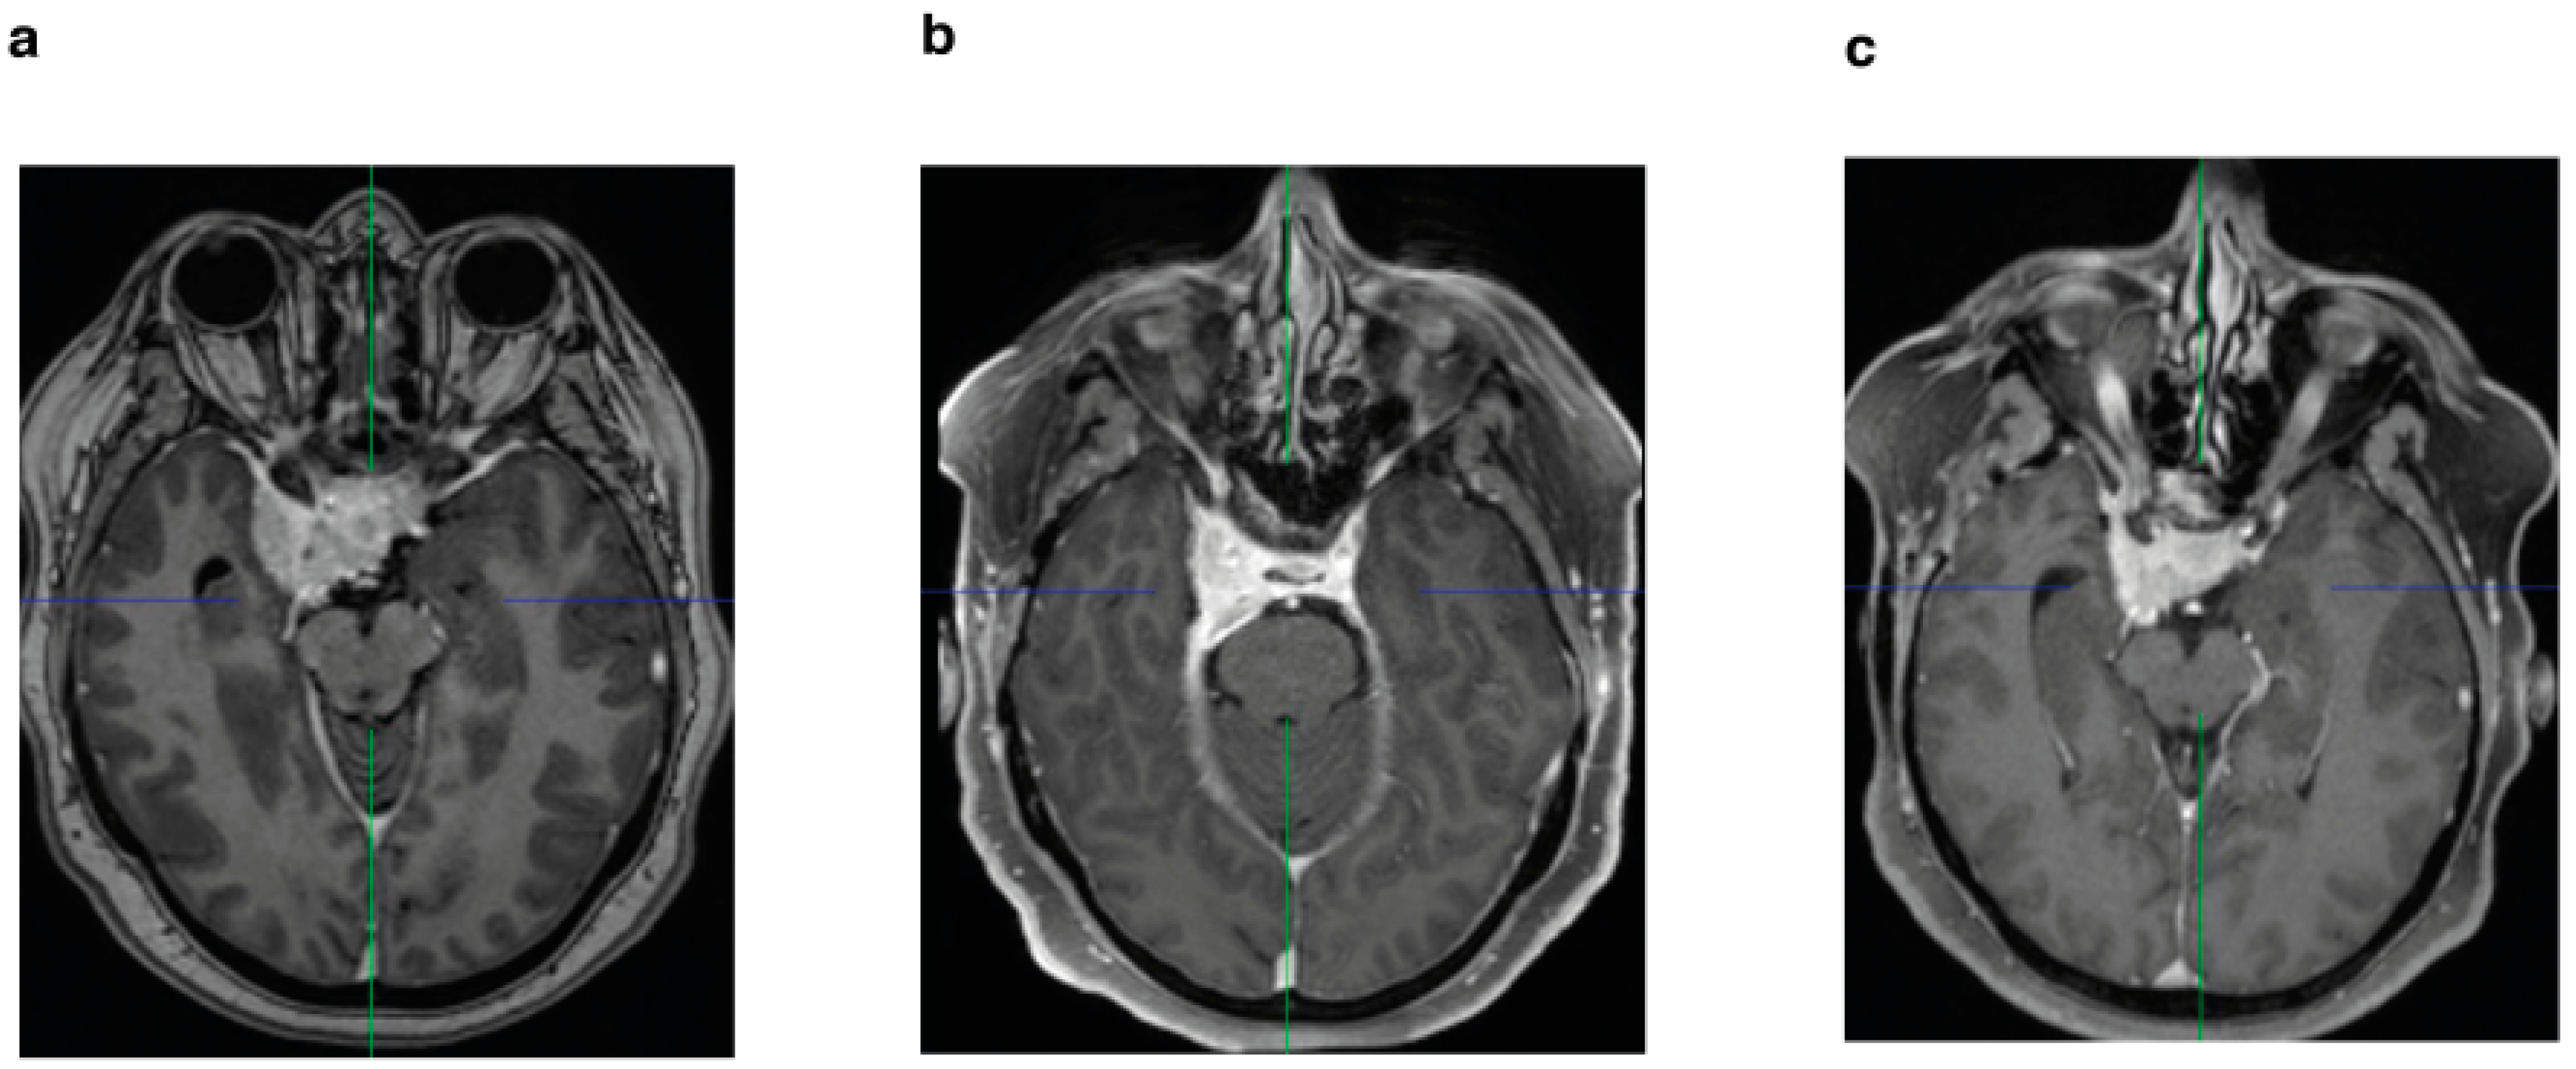

3.2. Postoperative Adjuvant Radiotherapy in WHO Grade I Meningioma

Thirty-five patients (37%) were treated postoperatively with stereotactic radiotherapy of the residual tumor in the cavernous sinus (Figure 4a), of which three patients had tumor recurrence/progression (3.1%). In contrast, 60 patients (63%) underwent surgery alone, of which 24 patients (25.2%) had tumor recurrence/progression. Both the Kaplan–Meier analysis (p = 0.0002) (Figure 4b) and the univariate (p = 0.0032) and multivariate analysis (p ≤ 0.0001) showed significant differences for the two groups (Figure 5) (Table 2).

Figure 4. (a) Diagram of enrolled medial sphenoid wing meningioma based on therapy (surgery only vs. surgery plus radiotherapy); (b) Kaplan–Meier curve: PFS in relation to therapy (surgery only vs. surgery plus radiotherapy) in WHO grade I meningioma.

In our study, Kaplan–Meier analysis showed prolonged PFS in patients who received adjuvant radiotherapy (Figure 4b), as did the additional multivariate analysis that showed significantly better PFS (Table 2). These results are in line with other studies [11,13,14,15,27]. The meta-analysis performed by Sughrue et al. (2010a) showed the superiority of radiation treatment over surgical resection in terms of preserving cranial nerve function in cavernous sinus meningioma. Nevertheless, they emphasized the importance of long-term follow-up after radiotherapy due to the potential for aggressive growth [11]. There is strong evidence for the primarily use of stereotactic radiotherapy in meningiomas invading the cavernous sinus. However, this is limited by the size of the tumor, its extracavernous extent, and the proximity to radiosensitive vital nerve tissue. In addition, cavernous sinus meningiomas and sphenoid wing meningiomas are two types of tumors that differ in their origin, behavior, and clinical manifestation. In most cases, sphenoid wing meningiomas become clinically apparent after they reach a certain size and infiltrate the cavernous sinus. Therefore, many authors recommend surgical decompression first to reduce the proximity of these lesions to the optic nerve, diencephalon, and brainstem, followed by radiotherapy to reduce morbidity [11,14,15].